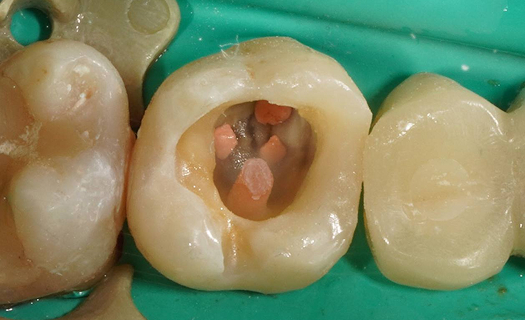

Перелечивание зуба с кистой под микроскопом

Проблема: У пациента отек щеки, боли самопроизвольные, усиливающиеся при приеме пищи, неудачное первичное лечение зуба (старыми методами).

Лечение: Проведено эндодонтическое перелечивание зуба под дентальным микроскопом, что позволило точно выявить анатомические особенности корневых каналов и устранить последствия ранее некачественного лечения. После купирования воспалительного процесса (киста) каналы герметично запломбированы. Коронковая часть зуба восстановлена для сохранения функции и герметичности до этапа постоянного протезирования.

Результат: После проведённого лечения болевые ощущения полностью устранены, отёк щеки исчез, воспалительный процесс купирован. Зуб сохранён, восстановлена его функция. Установлена коронка, что позволило полностью восстановить анатомическую форму и жевательную эффективность зуба.